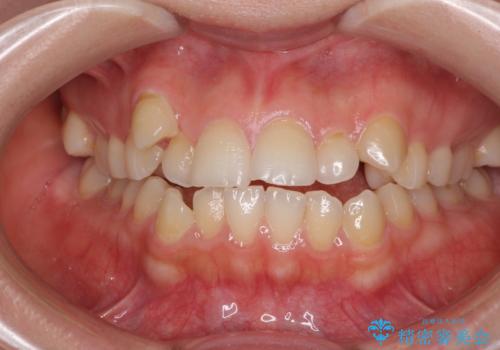

顕著な八重歯をインビザラインで治せるところまで改善